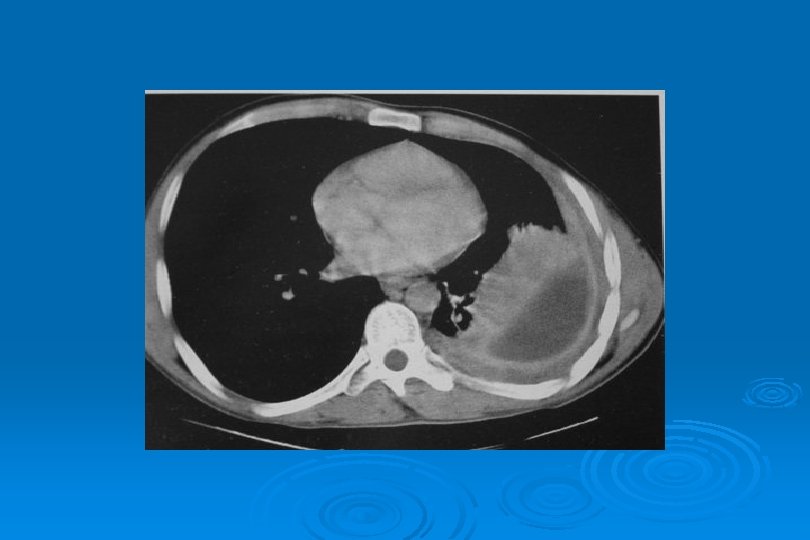

MİKOPLAZMA PNÖMONİSİ Yamalı, segmental veya lobar konsolidasyon veya buzlu cam yoğunluğu Ø İnterstisyumda kalınlaşma Ø Mozaik perfüzyon Ø

M. Pneumoniae Pnömonisi